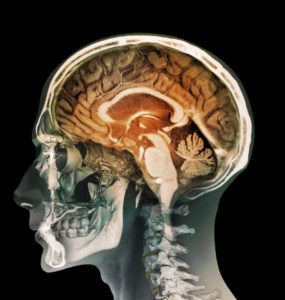

اليقظة - لغز القرن العشرين

تخيل معي أن تستيقظ فجأة من النوم، تخبرك مرآتك وكل من حولك أنك لم تعد في الثانية والعشرين من عمرك كما تتذكر بل تشعر كأنك عجوز فقدت من عمرك عشرات وعشرات السنين أين وكيف أنت لا تعلم؛ شاخ جسدك وحده دون إخبارك... هذا ما حدث...